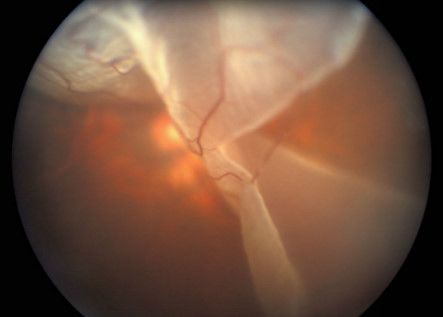

5、视网膜脱落

已经液化的玻璃体,通过视网膜裂孔流入到视网膜神经上皮层与色素上皮层之间, 形成视网膜脱落。

视网膜脱离